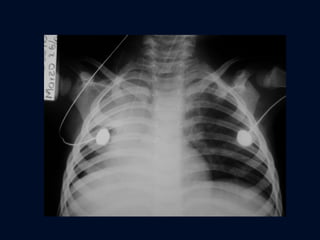

ATELECTASIA PULMONAR TOTAL Opacidad  del hemitórax Elevación del hemidiafragma  Desviación completa del mediastino Sobreinsuflación que pasa la línea media

ATELECTASIA PULMONAR TOTAL